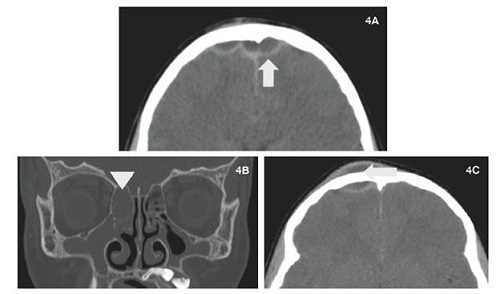

Caso 4

Paciente masculino de 13 años consultó por 4 días de evolución de cefalea y edema periorbitario derecho. Se diagnosticó celulitis facial y se inició antibioticoterapia, aunque presentó tumefacción en región frontal dos días después. Se hizo un cuadro hemático, que mostró leucocitosis y neutrofilia. La tomografía de cráneo simple evidenció empiema epidural frontal de 10mm asociado a colección liquida de tejidos frontales y sinusitis frontal, hallazgos compatibles con el pseudotumor inflamatorio de Pott con compromiso intracraneal. Se interconsultó con el servicio de ORL y neurocirugía, quienes consideraron manejo quirúrgico y antibioticoterapia por seis semanas, con lo cual el paciente exhibió una adecuada evolución clínica (Figura 4).